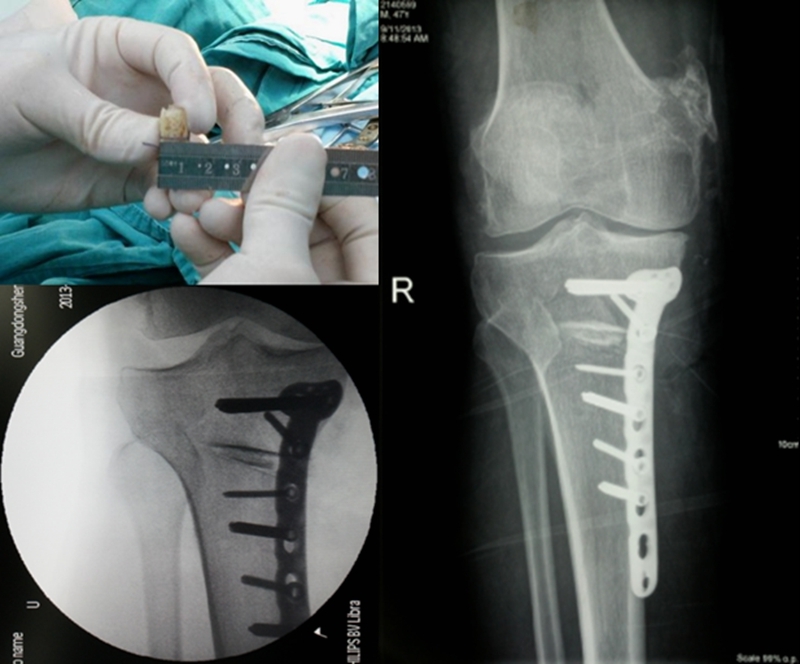

病例

病例1:46岁,滑雪运动员,多发韧带伤,内翻畸形膝关节疼痛,开式截骨后二月全负重行走,膝关节疼痛缓解

病例2:男性,19岁,因发现右膝关节内翻、过伸畸形伴跛行5年(左侧膝关节也有类似畸形,暂时无症状)。于2006年7月就诊,其母亲也有类似病史。查体:右膝关节内翻畸形约15度,应力下过伸约20度,内翻及外翻时膝关节均有松动感,Lanchman试验(+)。无负重下X片示:右膝关节内翻畸形约15度,胫骨平台无后倾,倒呈前倾13º。膝关节MR示:右膝内侧股骨及胫骨软骨面已有缺损并囊性变。诊断:先天性膝关节内翻畸形(Blount病)。

术前X线可见右膝关节内翻畸形约15°,胫骨平台前倾畸形13°

术前膝关节MR示:右膝内侧胫、股骨骨软骨面已有缺损并囊性变

应力位过伸畸形明显

术后6月X片示右膝内翻、前倾畸形已矫正,胫骨截骨处愈合,腓骨未愈合,但无症状。